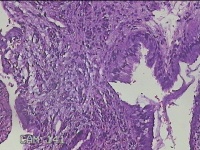

宫颈6点、10点、12点组织

性别

女

年龄

30岁

临床诊断

女性盆腔炎;宫颈炎性疾病;异常子宫出血

一般病史

宫颈HPV-56(+),TCT见非典型鳞状上皮细胞

标本名称

大体所见

1.“宫颈6点组织”:灰白暗红色不规则组织0.5x0.3x0.2cm一块。 2.“宫颈10点组织”:灰白暗红色不规则组织0.3x0.2x0.1cm一块。 3.“宫颈12点组织”:灰白暗红色不规则组织0.8x0.5x0.3cm两块。

图2

CIN1